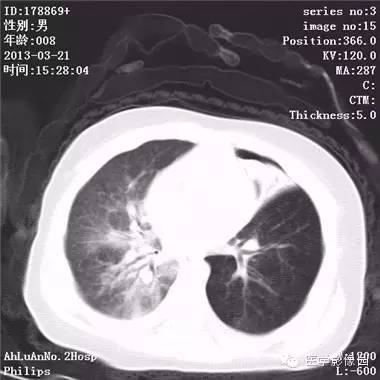

患儿男,8个月,呛咳,发热一周。实验室检查白细胞及中性粒细胞增高。

两肺肺纹理增多、增粗,右肺可见斑片状、片絮状模糊影,边界欠清;左肺上叶见楔形高密度影,内可见支气管征,尖端指向肺门;左肺下叶肺野透亮度增强;另见左肺主支气管内可见块状软组织密度影。

支气管异物(花生米)伴两肺炎症(追问病史,患儿奶奶层于一周前喂食患儿花生米,当时疑似“呛进去”,后来见好了也就没留意)。